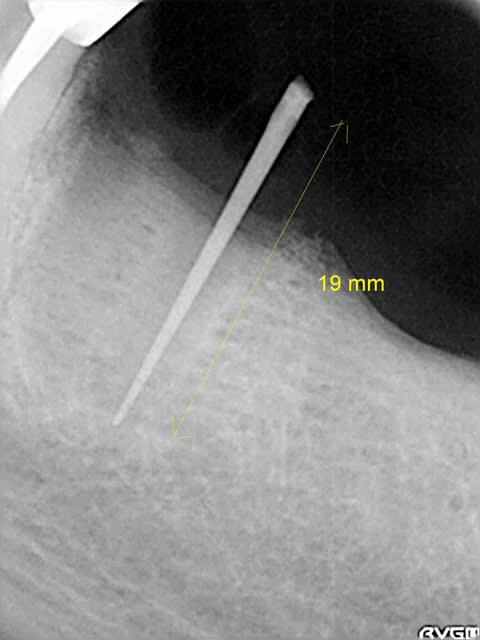

derniere radio faite avec angulateur .... et en mars 2010

le cone apres extr dans l'alveole mesure 19 mm et avec la radio je mesure 18 mm : il y a peu de deformation